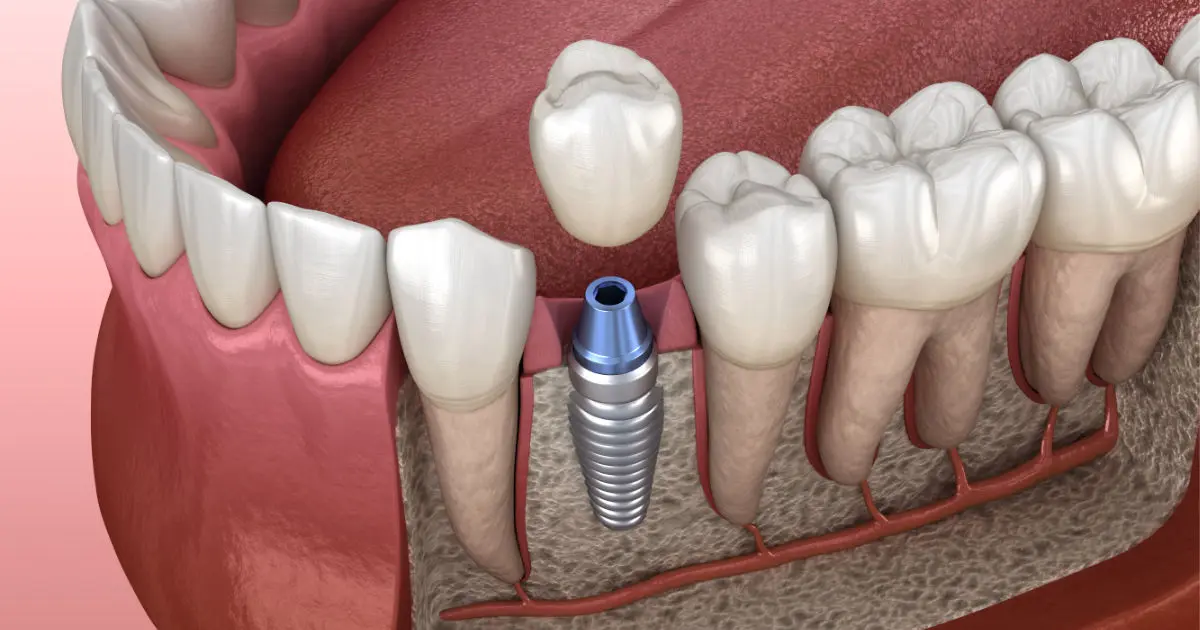

Recuperá tu Sonrisa

con Implantes de Titanio

Volvé a comer, hablar y sonreír con total seguridad. Utilizamos tecnología de vanguardia y materiales biocompatibles de alta gama para reponer tus piezas dentales de forma definitiva y natural.

Fijación Firme y Segura

Material Biocompatible

Estética Indistinguible

Cirugía Mínimamente Invasiva

Implantes Dentales

Solución fija y duradera para reemplazar dientes perdidos con un resultado natural y funcional.